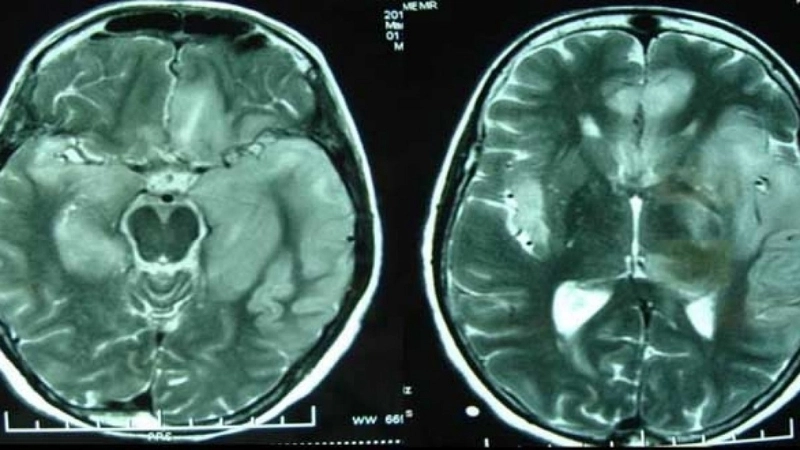

Image description of Murray Valley Encephalitis

Murray Valley Encephalitis is a rare but serious viral infection transmitted by mosquitoes, primarily affecting the brain and nervous system, with potential life-threatening complications.